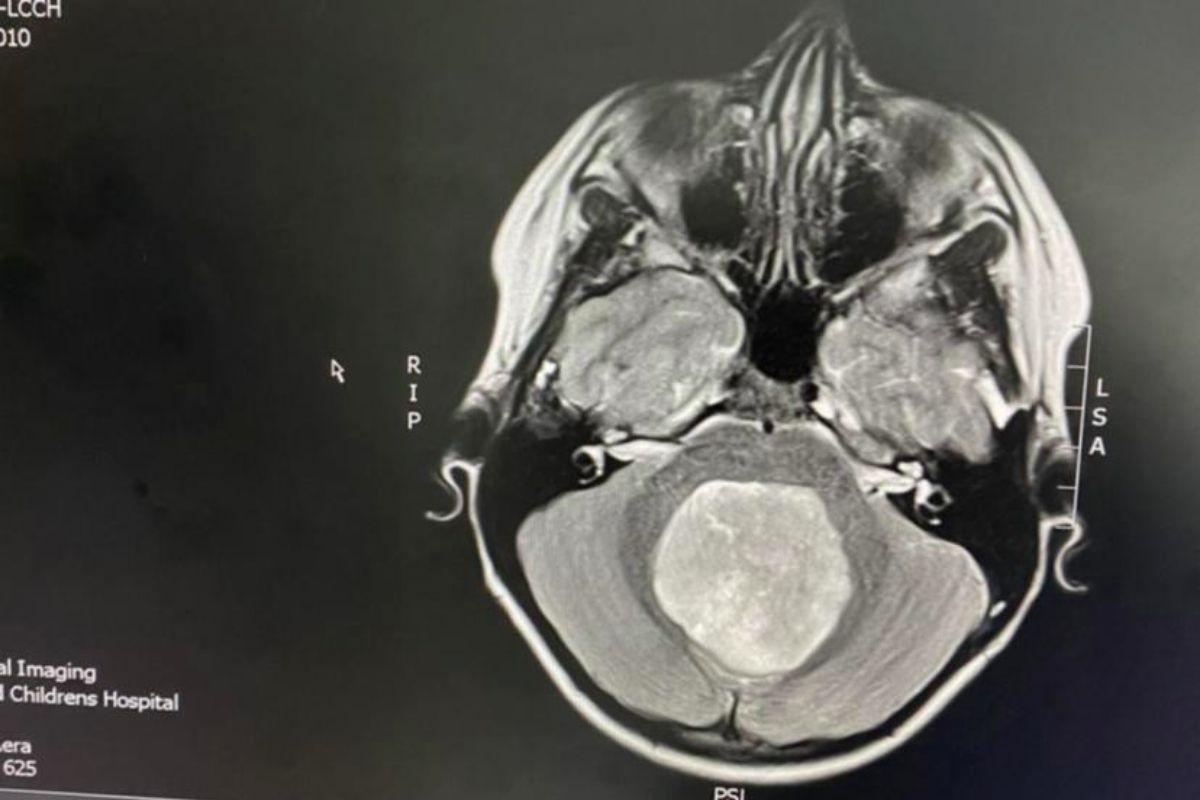

O tumor de Luca tinha o tamanho de uma bola de tênis. Segundo os médicos, a massa dentro do crânio do garoto media aproximadamente de 5 a 6 centímetros. Depois de um tempo os médicos ainda descobriram era um meduloblastoma (um tipo de tumor do cérebro) de grau 4.

O tumor da criança tinha o tamanho de uma bola de tênis (Foto: Reprodução/ 7News)

No meio do procedimento os médicos pararam por um tempo para levá-lo a outro exame de ressonância magnética, no qual descobriram que o tumor tinha crescido no tronco cerebral de Luca. O que significava que eles não conseguiriam tirar tudo com o bisturi, tendo que submetê-lo a seis semanas de radiação e sete rodadas de quimioterapia.